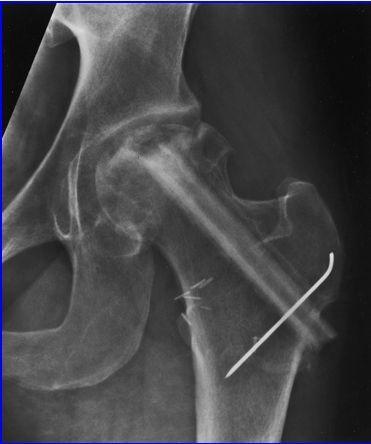

SE APRECIA UNA LINEA DE COLAPSO SUBCONDRAL EL SIGNO DE LA MEDIA LUNARADIOLOGIA NORMAL EL DIAG SE PUEDE REALIZAR POR RESONANCIA MAG

Secuencias Radiológicas